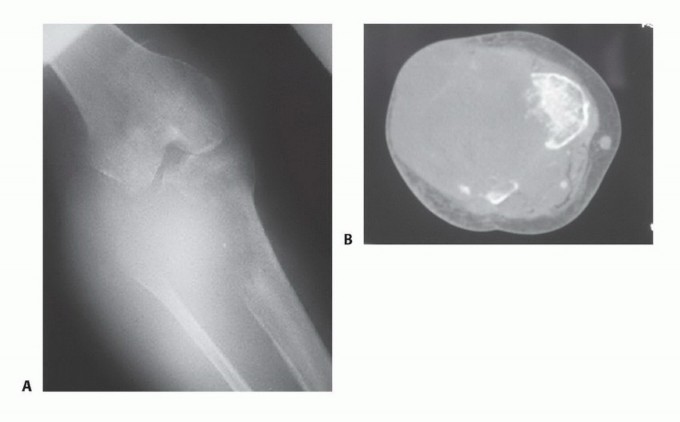

- الكسور المرضية: حدوث كسر في عظم الفخذ نتيجة لضعف العظم بسبب الورم، حتى مع إصابة طفيفة أو بدون إصابة واضحة.

- الأشعة السينية (Plain Radiography): غالبًا ما توفر الأشعة السينية أول إشارة للحاجة إلى البتر وتقدير مبدئي لمستوى البتر المطلوب. يمكن أن تكون الصور العرضية لعظم الفخذ والساق مفيدة في إظهار انتشار الورم ومدى تدمير العظام. ومع ذلك، قد لا تظهر النتائج الإشعاعية إلا بعد تدمير ما يصل إلى 30% من بنية العظم.

- التصوير المقطعي المحوسب (CT) والتصوير بالرنين المغناطيسي (MRI): تعتبر هذه التقنيات الأكثر فائدة في تحديد مستوى انتشار الورم داخل النخاع العظمي ومدى انتشاره خارج العظم، وهو ما يستخدم لتحديد مستوى البتر. يُعد التصوير بالرنين المغناطيسي أيضًا مفيدًا لإظهار انتشار الورم في الهياكل العصبية الوعائية، مما يستدعي البتر غالبًا. كما أنه الدراسة التصويرية الأكثر موثوقية في تحديد وجود النقائل القافزة (skip metastases)، والتي قد تغير مستوى البتر.